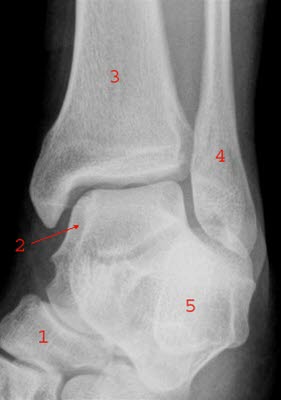

Ankelleddene er meget utsatte for skader fordi de er ganske bevegelige og belastes med hele kroppens tyngde. Leddet utgjøres av fire ben: skinnbeinet (tibia), leggbeinet (fibula), hælbeinet (calcaneus) og ankelbeinet (talus). Ankelleddet stabiliseres av ankelgaffelens form og leddbånd på innsiden (medialt), utsiden (lateralt) og mellom de to leggbeina (syndesmosen - et bånd som binder sammen de to beina). Se illustrasjon av ankelleddet nedenfor sett bakfra og fra siden, og røntgenbilde tatt skrått bakfra og fra siden.

Ved mistanke om brudd tas røntgenbilder av ankelen i ulike retninger. Det er viktig å ta bilde av fibula i hele sin lengde. Ofte foreligger flere brudd eller skader. Noen ganger er det nødvendig å ta CT for å klargjøre omfanget av brudd, særlig ved brudd i selve leddet.